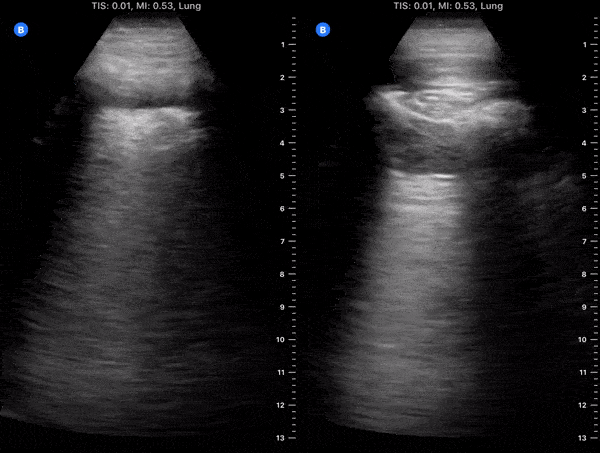

Pulmonary - Hospitalized COVID-19+ Patient on Day 9 of Symptoms [1/2]

These clips are taken from a patient admitted with COVID-19 pneumonia. The patient was on day 9 of symptoms. His cough had improved and fever resolved however he had hypoxia requiring supplemental oxygen. Left clip: Lung ultrasound of right lower lobe demonstrating thickened irregular pleura, diffuse b lines (confluent) with scattered puntate subpleural consolidation and small effusion overlying pleural effusion. Right clip: Lung ultrasound of right upper lobe demonstrating a moderate subpleural consolidation with air bronchograms present. Image courtesy of Fritz Fuller (@POCUS_Society)